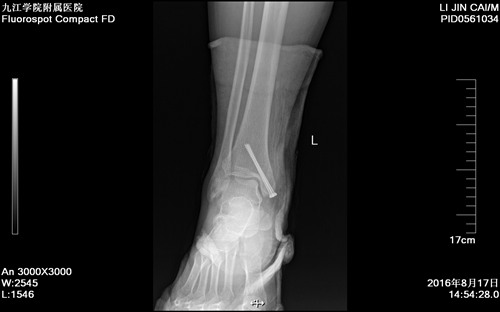

术后复查X线片显示患者骨折复位良好,螺钉位置佳